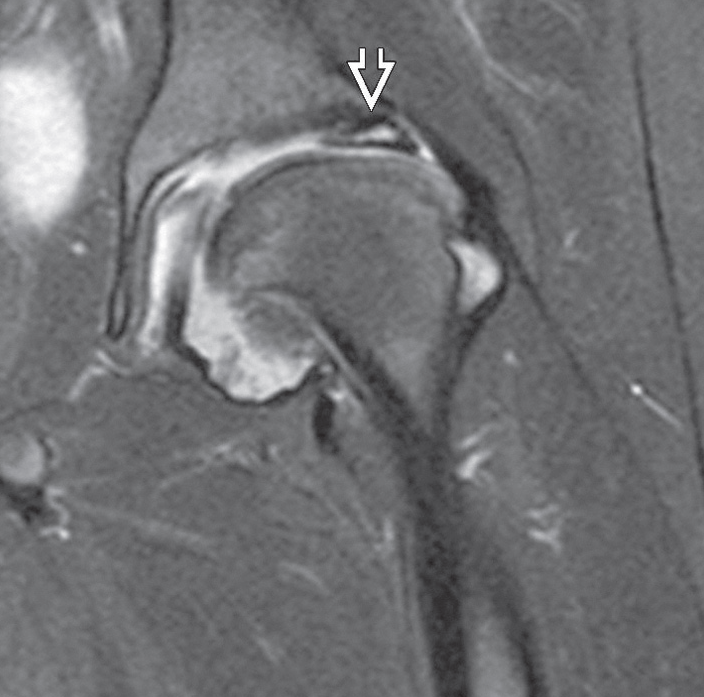

Hastanın teşhisini koymak ve hangi derecede kireçlenmesi olduğunu anlamak için birtakım tanı yöntemleri kullanılır. Hastanın şikayeti ve hikayesinden kalça ağrısının boyutu ve bunun günlük aktiviteleri etkileme derecesi hakkında bilgi sahibi olunur. Takiben fiziksel muayene ile kalça hareketliliği ve gücü değerlendirilir. Fiziki muayenenin ardından yıpranmanın kesin tanısı, boyutu ve nedenlerinin tespiti için röntgen çekilir. Bazen kalçadaki kemik ve yumuşak dokuların durumunu belirlemek için manyetik rezonans görüntüleme (MRG) taraması gibi başka testlere de ihtiyaç duyulabilir.

Perthes hastalığına bağlı kalça kireçlenmesinin MR görüntüsü